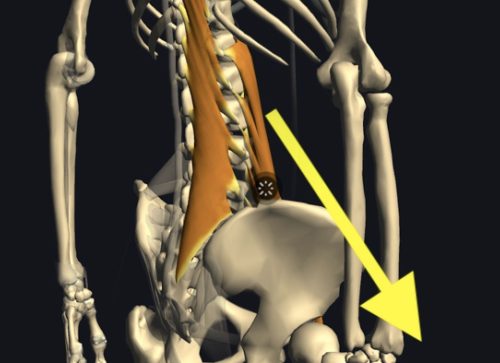

大腰筋が腰椎を圧迫

僕の経験による腰椎椎間板ヘルニアの本当の原因は大腰筋にあります。

この大腰筋ですが

主な役割:股関節を安定させる、歩く際に脚を挙げる働きをします。

起始停止:起始部は胸椎(T12)から腰椎(L1~5)の横突起で、大腿骨の小転子に停止します。

となっております。

つまり足の付け根部分と腰椎を結んでいる筋肉なのです。

腰椎椎間板ヘルニアが大腰筋の硬直等により発症するメカニズ�

硬直した大腿部が大腰筋を下方向に引っ張ったり、大腿骨頭の位置ずれが起きて大腰筋が下方向へ強く引っ張られたり、大腰筋そのものが硬直した場合に 起始部として付着している腰椎1〜5の何れかに負荷をかけてしまい圧迫が起き、押しつぶされた軟骨が変形したり 飛び出したりするのではないか?とい仮説を元に大腰筋を補正する施術をした結果98%もの方々の痛みが消失しただけでなく、飛び出していた軟骨も元に戻ったのです。

大腰筋が下方向に圧力をかけ椎間板が変形や飛び出しを起こす。

まずはこちらの図。大腰筋ですがこのように腰椎から足の付け根部分に接続されていますので、長時間座っていたり、立ち仕事の長い方、立ったりしゃがんだりを繰り返す方には負担が大きく硬直して縮むことで腰骨を足の方へ(下方向)引っ張ると先程説明しました。

大腰筋が硬直

硬直した腰筋が縮んで腰椎を下方へ圧迫